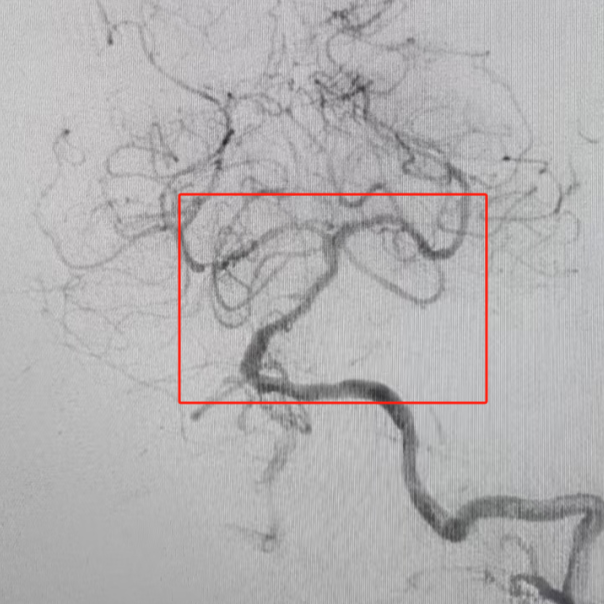

手术团队在影像引导下发现患者血管条件极差:双侧椎动脉扭曲,优势椎动脉开口处扭曲伴狭窄,基底动脉重度狭窄。主刀医师凭借丰富经验,建立导管通路。随后,团队精准实施颅内动脉取栓+基底动脉球囊扩张成型术,仅用40分钟便开通血管,恢复脑干及小脑血供。术中需克服血管迂曲、血栓逃逸等高风险因素,每一步操作均需毫米级精准控制,稍有不慎即可引发血管破裂或血栓扩散。